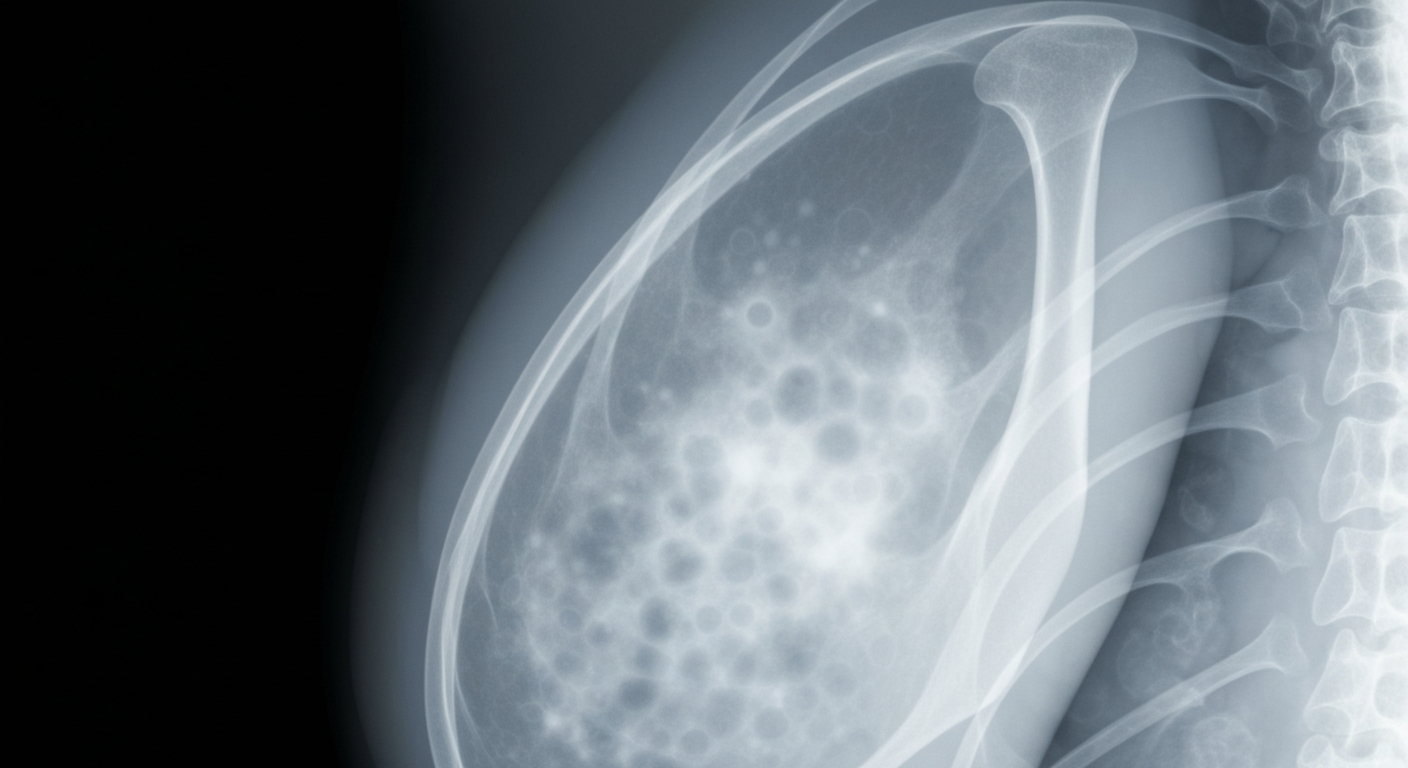

A ghostly X-ray image reveals the internal structures of Olivia Munn's breast, highlighting the cancer cells she bravely fought against with the support of her husband John Mulaney.Los Angeles TodayOlivia Munn is opening up about her recent breast cancer diagnosis and treatment, revealing how her husband John Mulaney was by her side every step of the way. Munn, 45, said Mulaney's humor and support helped her get through the darkest moments, including facing the 'possibility of death.' The couple, who married in 2024, share two young children together.

Munn was diagnosed with bilateral breast cancer in early 2023, shortly after testing negative for the BRCA gene. She underwent numerous operations, including a double mastectomy, lymph node dissection, reconstructive surgery, and a partial hysterectomy. Despite the physical and emotional toll, Munn said she has only cried twice, wanting to stay 'clearheaded' throughout her treatment. Mulaney was by her side for every doctor's appointment, using his notebook of joke ideas to help lighten the mood. Munn also found that returning to acting, with the help of an intimacy coordinator, aided in her recovery by making her feel more comfortable in her body.